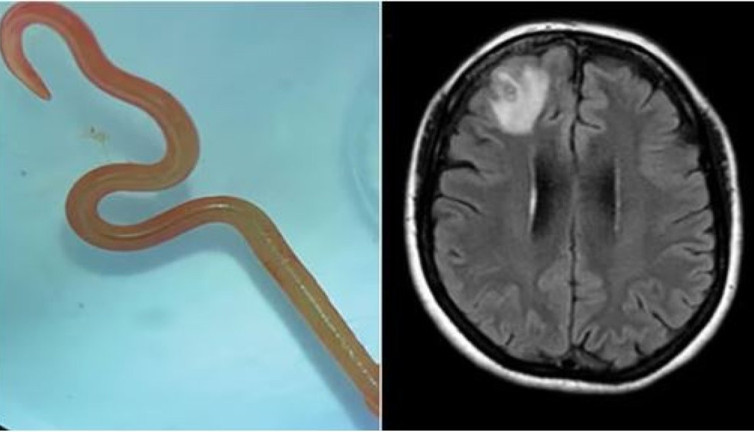

Kanberra hastanesi solucan